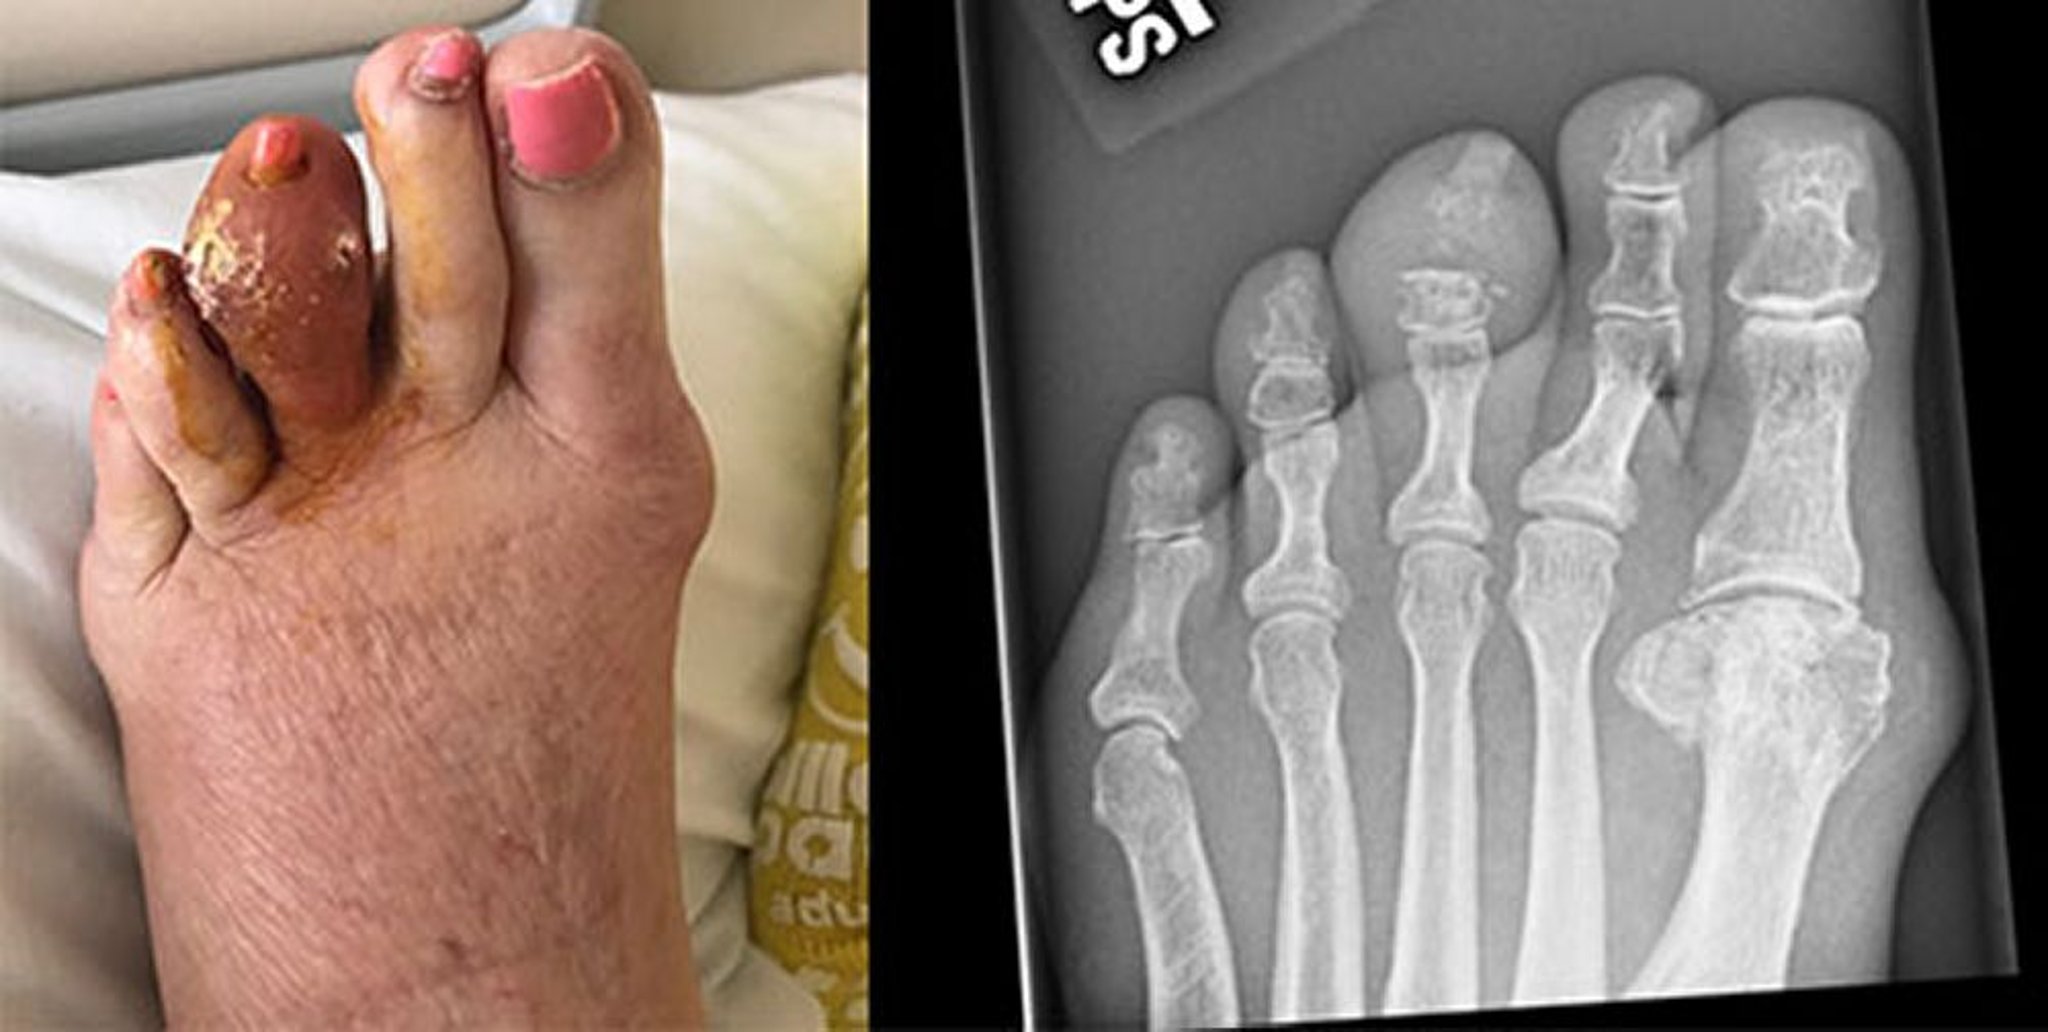

Подагра среднего пальца ноги

На этой фотографии изображен большой тофус на левом третьем пальце, который раскрылся с высвобождением затвердевших масс мочевой кислоты. На рентгеновском снимке справа видна эрозия средней фаланги и дистального межфалангового сустава.